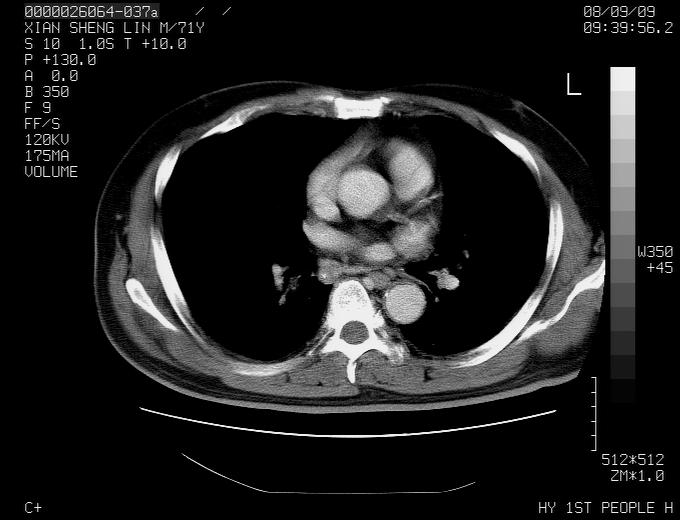

患者,男性,71岁,因咳嗽而就诊,

典型的右肺中心性肺癌并纵隔淋巴结转移

考虑右肺中心性肺癌并右肺门及纵隔淋巴结转移。

1,右肺中心型ca,气管隆突旁淋巴结转移。